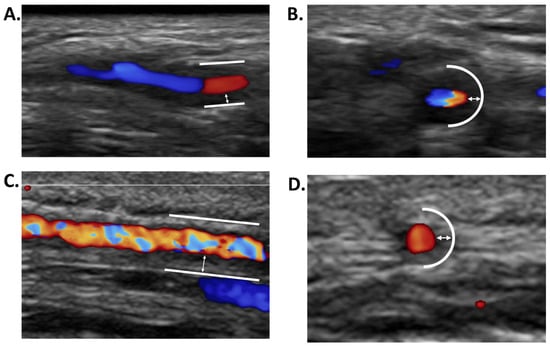

| GCA | Incidence: 14.6 (range: 6.0–43.6) per 100,000 persons aged ≥50 years [73] Prevalence: 75.5 per 100,000 inhabitants (107.8 in women, 40.1 in men) [74] | - Headache, scalp tenderness, or jaw claudication.Abnormal TA exam: induration, tenderness to palpation, edema, decrease/abolition of the temporal pulses - No involvement of the intracerebral vessels. | - PMR - Claudication of a limb - Abolition/decrease of a peripheral pulse - Aortic complication (aneurysm, dissection) - Ischemic complications: Ophthalmological: AAION, CRAO, PION, diplopia Neurological: Stroke (posterior vertebral territory) Myocardial infarction, limb ischemia | - Inflammatory syndrome (95%) - Inflammatory anemia, thrombocytosis (40–50%) | Granulomatous, non-necrotizing panarteritis, inflammatory cellular infiltrate of the media and/or intima made of mononuclear cells, multinuclear giant cells, fragmentation of the internal elastic lamina, destruction of the media, stenosing hyperplasia of the intima | - Glucocorticoids (constant effectiveness except for ischemic sequelae) - 2nd line (relapse(s), corticodependence): tocilizumab, methotrexate |

- De Miguel, E.; Beltran, L.M.; Monjo, I.; Deodati, F.; Schmidt, W.A.; Garcia-Puig, J. Atherosclerosis as a potential pitfall in the diagnosis of giant cell arteritis. Rheumatology 2018, 57, 318–321. [Google Scholar] [CrossRef] [PubMed]